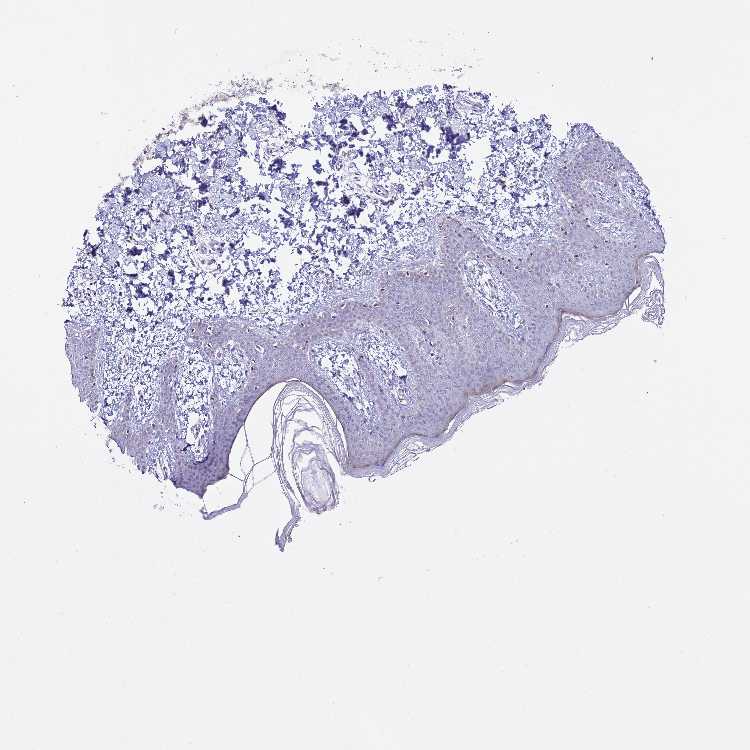

SKIN 1 - Antibody stainingi

Antibody staining in the annotated cell types in the current human tissue is reported as not detected, low, medium, or high, based on conventional immunohistochemistry profiling in selected tissues. This score is based on the combination of the staining intensity and fraction of stained cells.

Each image is clickable and will lead to virtual microscopy that enables deeper exploration of all samples and also displays staining intensity scores, fraction scores and subcellular localization as well as patient and tissue information for each sample.

Antibody HPA046377

Langerhans Not detected

Fibroblasts Not detected

Keratinocytes Not detected

Melanocytes Not detected

SKIN 2 - Antibody stainingi

Epidermal cells Low